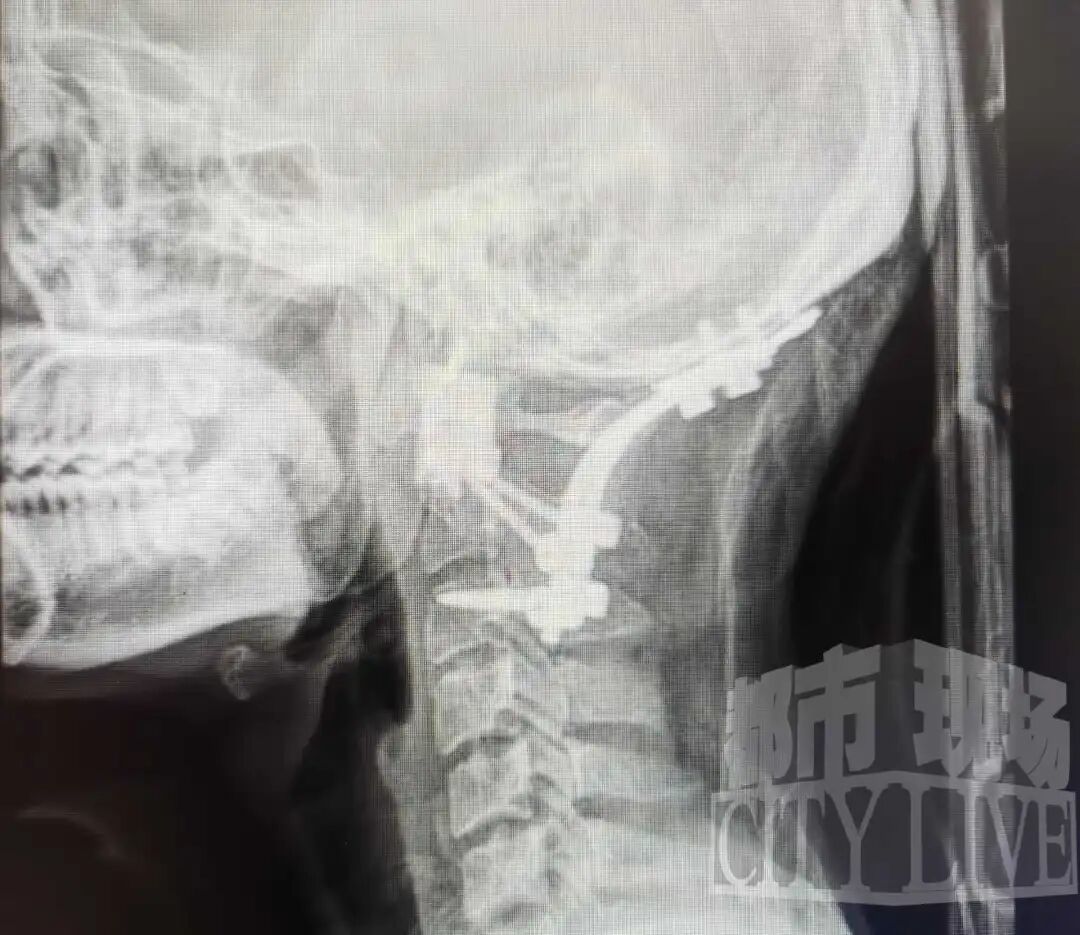

检查结果让所有人都捏了把汗:赖先生的寰椎部位长了一个巨大肿瘤。这个位置非同小可,它就像“顶梁柱”,承托着头颈的所有活动,里面更是包裹着生命中枢——延髓和脊髓。这种疾病非常罕见,赖先生赶紧从宜春转到南昌求医。医生们一看,情况确实非常复杂。

南昌大学一附院骨科医院副院长、主任医师姚浩群告诉《都市现场》记者,团队通过3D打印模型清晰展示了肿瘤的复杂情况:它从第一颈椎长出,缠绕着关键的椎动脉向前生长至咽后壁,紧邻食道、气道和重要脊髓神经,严重破坏骨质。若肿瘤继续发展,无论向后压迫延髓导致呼吸衰竭,还是向前生长引发气道梗阻,都将危及生命。

寰枢椎手术本就是脊柱外科“皇冠上的明珠”,肿瘤切除更是难上加难。为确保万无一失,医院集结了麻醉、影像、康复等多学科精英,还利用3D打印技术为他“量身定制”了人工椎体。11月26日,手术正式开始,仅用四个小时,病灶被完整摘除。

姚浩群医生介绍,手术的关键在于小心分离被肿瘤包裹的椎动脉,之后切断与正常骨质的连接,将肿瘤完整取出,并利用3D打印的人工椎体进行精准重建,完美恢复了该部位的稳定性。